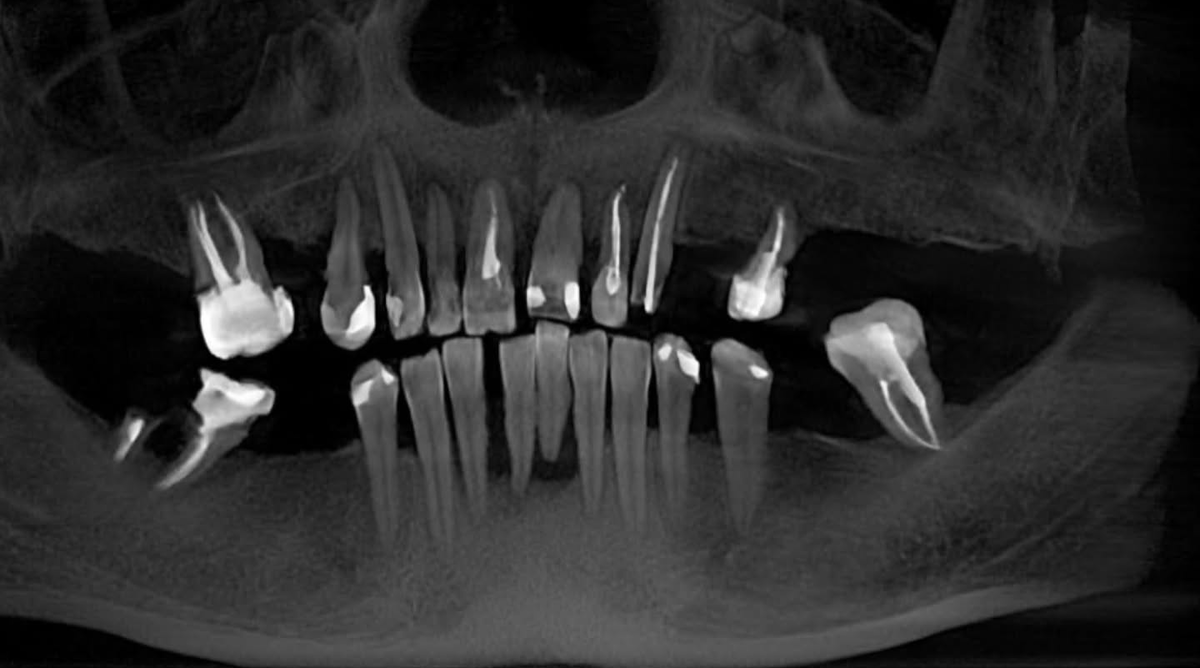

Фото нашей пациентки на момент обращения в клинику.